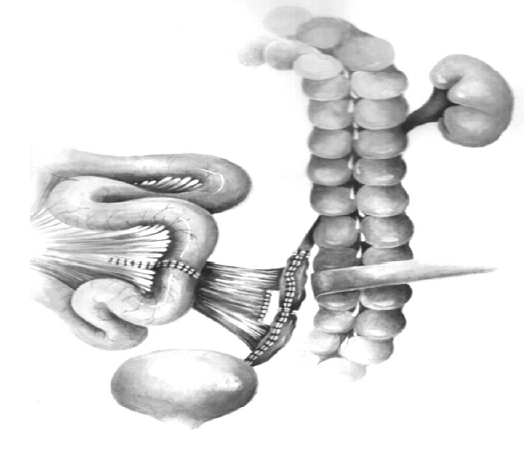

Bilateral small intestinal reconstruction of the ureters was performed in 40 (20.7%) patients. Most often, in 24 (60.0%) patients, U-shaped ileoureteroplasty was performed (Figs. 8 and 9), and more complex reconstructions were performed less often; that is, Y-shaped in 1 (2.5%) case, J-shaped in 3 (7.5%), L- and 7-shaped (Figs. 10 and 11) ileoureteroplasty in 6 (15.0%), and that with two separate ileografts in 6 (15.0%) cases.

Fig. 8. Bilateral U-shaped ileoureteroplasty

Fig. 10. Bilateral isoperistaltic 7-shaped ileoureteroplasty